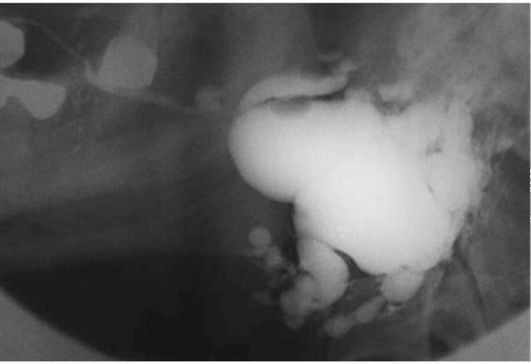

Выделяют начальную, клинически выраженную и позднюю стадии синдрома Шегрена. Начальная стадия обычно своевременно не диагностируется из-за отсутствия явных объективных и субъективных признаков болезни. Сухость рта бывает периодической, усиливающейся при физическом или эмоциональном напряжении. На сиалограмме обнаруживают мелкоточечные полости в паренхиме. В выраженной и поздней стадиях нарастают признаки постоянной ксеростомии. Отмечается быстрое прогрессирование кариеса, дисбактериоз слизистой оболочки полости рта. На сиалограмме выявляют большое количество мелких и средних округлых полостей и выход контрастного вещества за пределы протоков (рис. 6.5).

image

Рис. 6.5. Синдром Шегрена. Сиалограмма правой поднижнечелюстной железы. Определяется выход контрастного вещества за пределы протоков